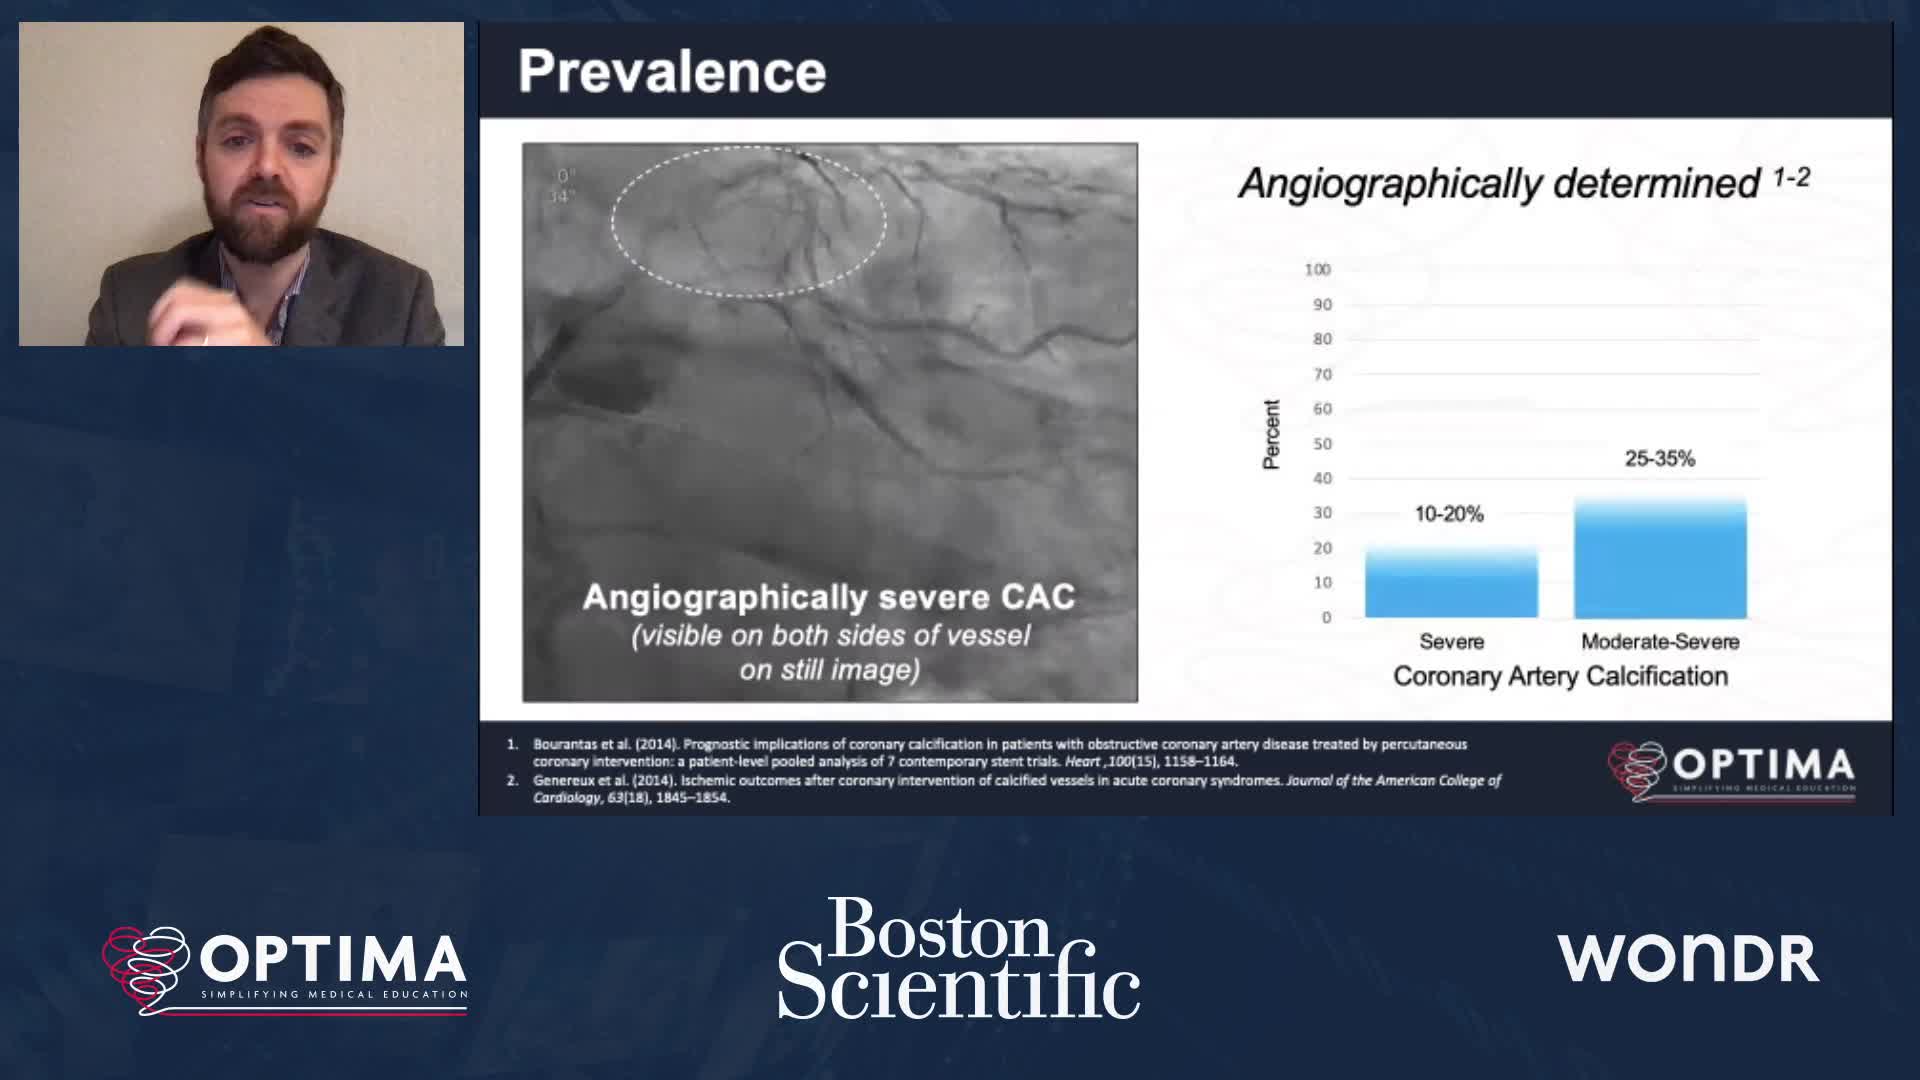

Calcium webinar with Boston Scientific

Treatment of coronary arterial calcium (CAC) has being redefined. We explore the interaction between CAC and patient...